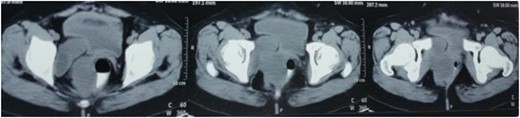

With a differential diagnosis of sciatic hernia or posterolateral perianal hernia in mind the patient was investigated further. A local ultrasound scan was suggestive of an ischiorectal abscess herniating through the sciatic foramen (~130 cc in volume). Since the report did not correlate with the clinical scenario, a contrast-enhanced computerized tomography (CECT) of the abdomen and pelvis was performed which was suggestive of 4.2 × 5.7 × 7.9 cm ischiorectal abscess abutting the rectal wall on the right side with extension down posteriorly and a 3.5 × 4.5 × 3.9 cm cystic lesion posterior to the urinary bladder with a possibility of supralevator extension of the abscess (Fig. 1).